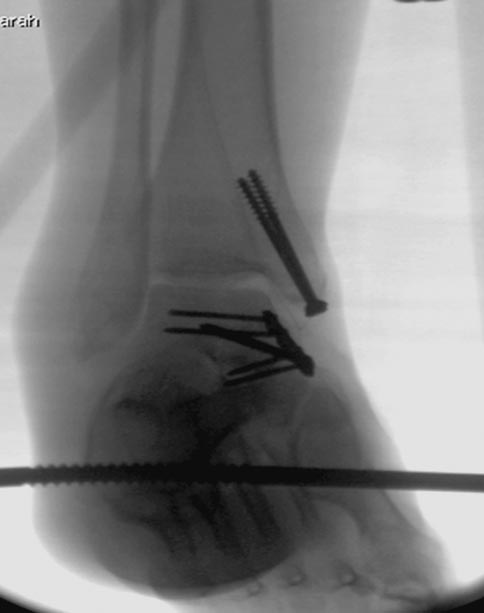

6 день госпитализации-операция на таранной кости.

Вложение не в текстовом формате было извлечено…

Имя     : Picture16.jpg

Тип     : image/jpeg

Размер  : 35001 байтов

Описание: отсутствует

Url     : http://weborto.net:8080/pipermail/ortho/attachments/20180416/07265245/attachment-0003.jpg